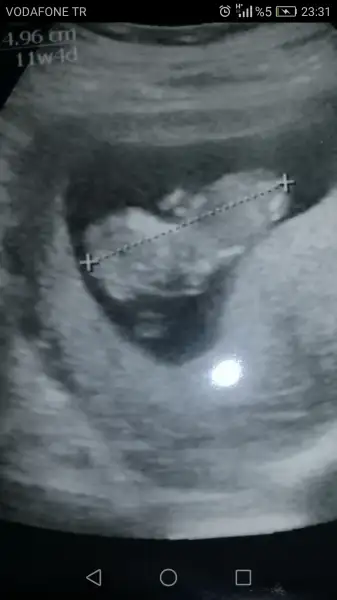

cnm insallah pazartesi hayirli haberler alirsinBenimkini benzettiler de cnm kismi mol diye bisi varmis nettede cok aciklama yok. Dr da emin olamadi beta hcg ye bakti yuksekmis biraz ama referans degerin icinde neye gore yuksekse pazartesi cagirdi bakalm ne dicek